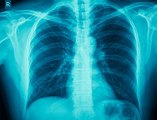

This Day in History: , German Scientist <br />Discovers X-Rays .<br />November 8, 1895.<br />Wilhelm Conrad Rontgen's , discovery of X-rays happened accidentally as he conducted a test on cathode rays.<br />He noticed a glow on a screen <br />coated with chemicals. <br />Rontgen called the rays <br />that caused the glow X-rays.<br />After conducting more experiments, <br />Rontgen discovered that X-rays could pass through <br />human flesh, but not harder substances such as bone.<br />He also learned that they could <br />be photographed. The discovery <br />was hailed as a medical miracle.<br />X-rays were first used on a <br />battlefield during the Balkan War in 1897.<br />Rontgen received the Nobel Prize in physics for his work but never attempted to gain financially for his discovery